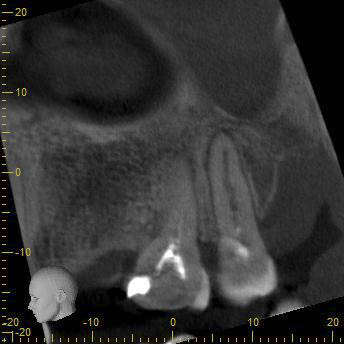

BN2627_DVT (3 von 17) Veröffentlicht 1. Dezember 2014 am 344 × 344 in Unerwartete Anatomie Zahn 26, 27- die WF